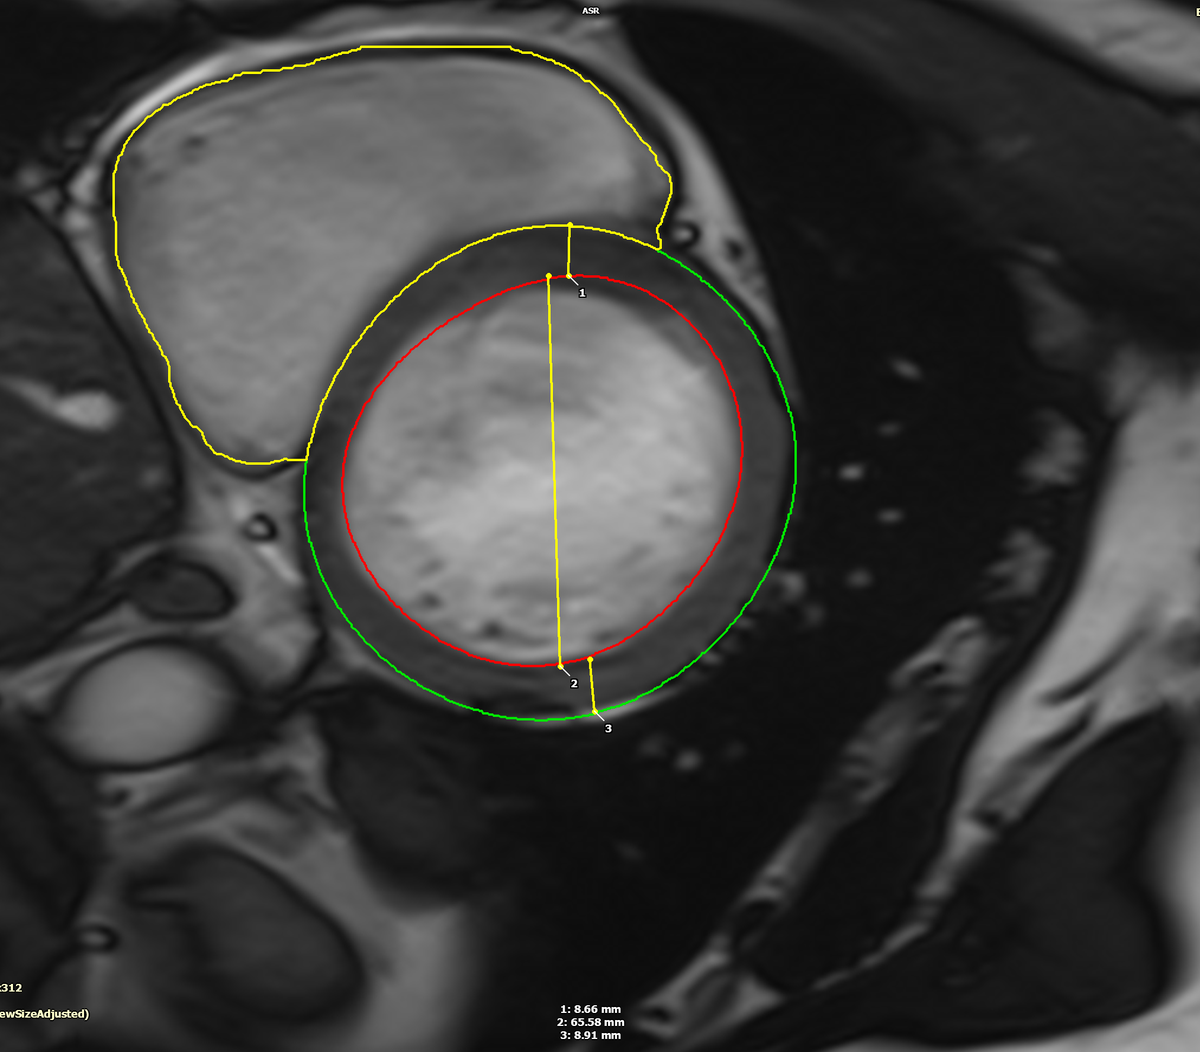

The convention in #whyCMR is to measure the LV linear dimensions in the slice distal to the MV as shown below which was 6.7 cm, consistent with the patient's LV volumes which were the severe range.

I went back and measured the LV dimension on #EchoFirst just distal to the basal septum. Lo and behold, the LV measured 6.7 cm.